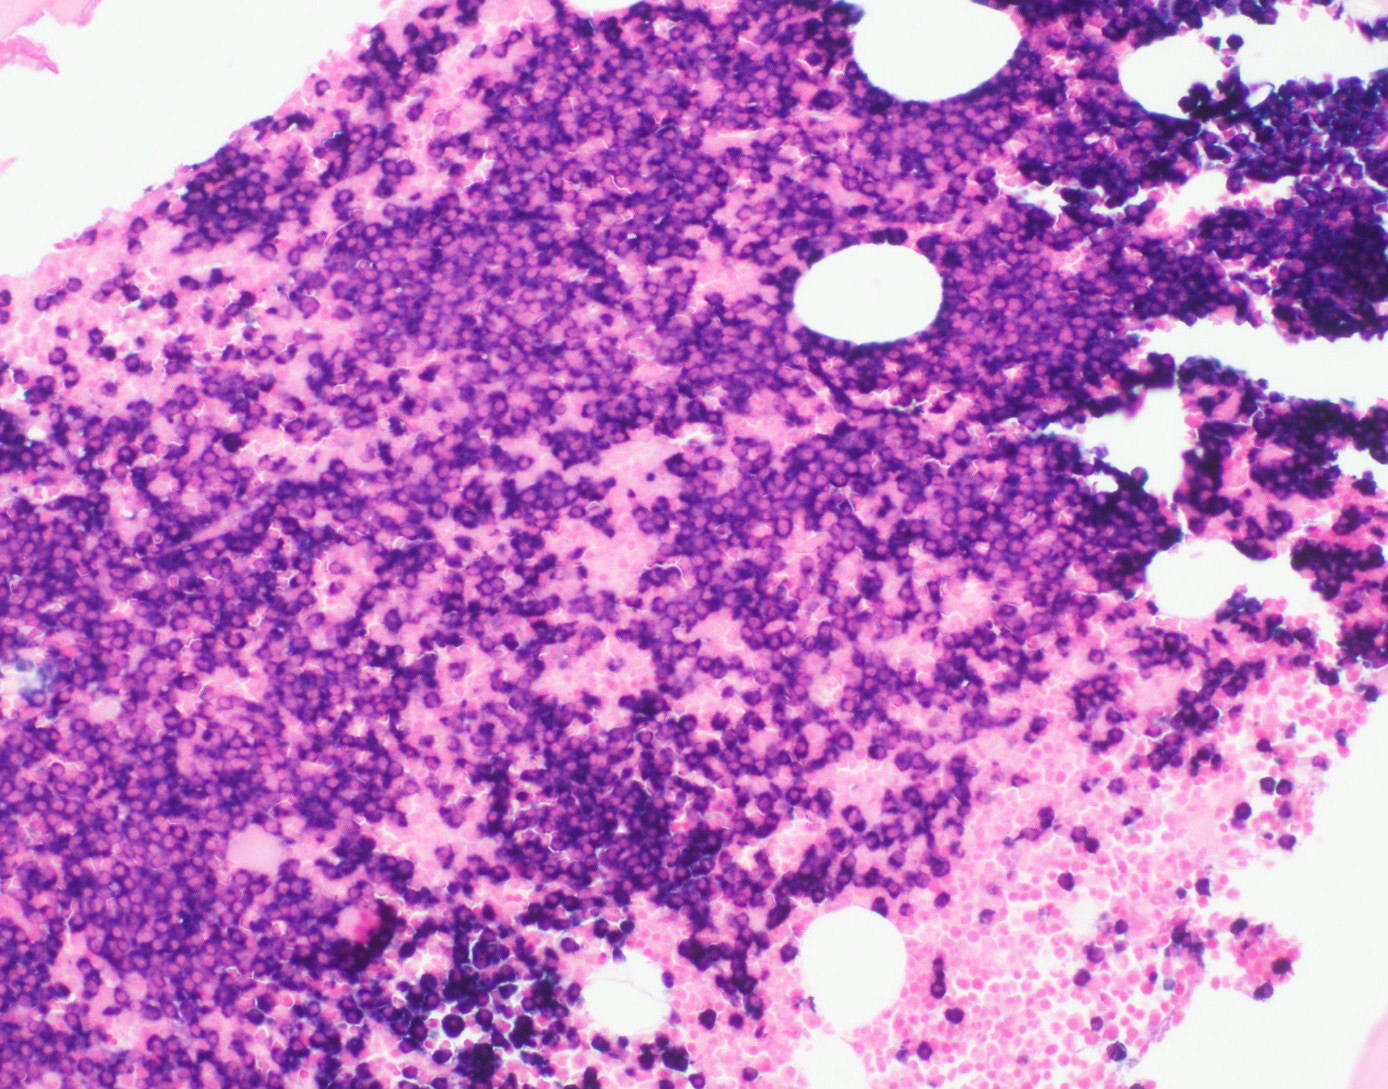

Microscopic (histologic) description

- Core biopsy (Am J Clin Path 1987;87:342):

- Interstitial clusters, nodules or sheets of plasma cells

- Areas of bone marrow may be spared with preserved hematopoiesis, other cases may have diffuse involvement and markedly suppressed hematopoiesis

- Prominent osteoclastic activity may be seen

- IHC to quantify plasma cells (CD138), stains for Ig kappa and lambda to establish clonality

Microscopic (histologic) images

Contributed by Genevieve M. Crane, M.D., Ph.D. and Tapan Bhavsar, M.D., Ph.D.